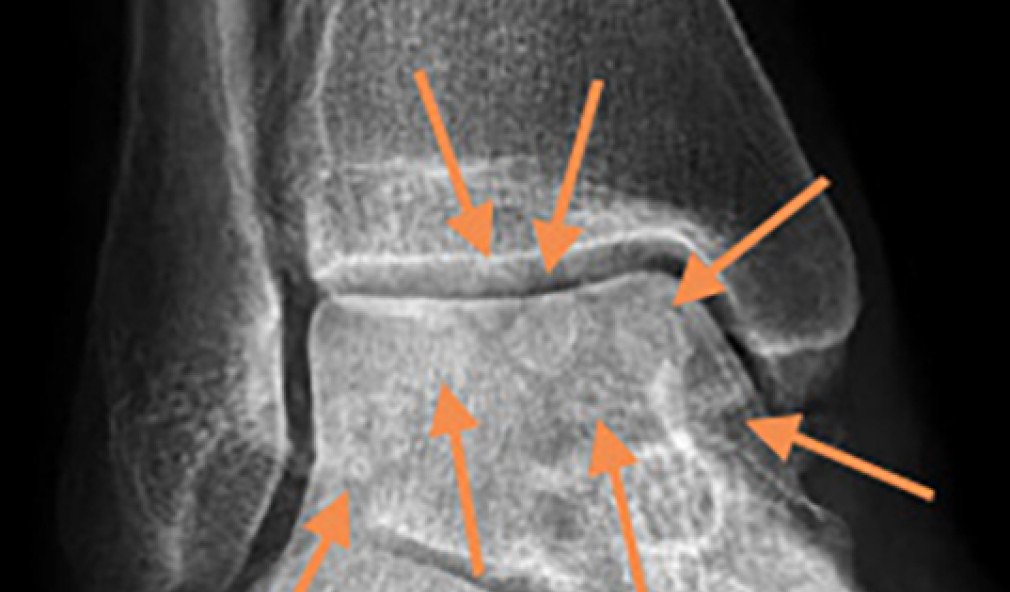

Read more about Fall des Monats – die juvenile Hallux valgus-Deformität

Röntgenbild juvenile Hallux valgus-Deformität

Fall des Monats – die juvenile Hallux valgus-Deformität

Die sportlich aktive 25-jährige Patientin litt an belastungsabhängigen Schmerzen unter dem linken Grosszehenballen. Sie berichtete uns, dass die Schmerzen schleichend kamen – zunächst tat der Fuss nur bei sportlichen Betätigungen wie z. B. beim Jogging weh, später dann auch bei normalen Alltagsbelastungen.